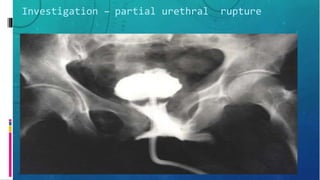

Investigation – partial urethral rupture

– Retrograde urethrography

• Confirms injury

• Location

• Severity

• Presence of foreign body

• Assoc injury e.g. Bladder